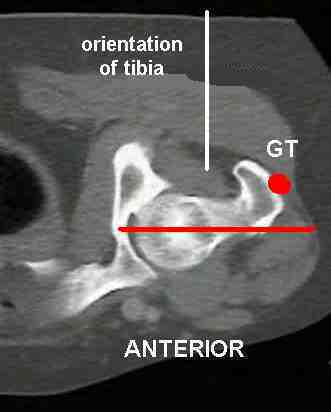

When the examiner palpates the greater trochanter (labelled "GT" in the figure to the right) with the hip in neutral rotation, it rests at a position that is slightly posterior to a frontal plane that passes through the acetabulum.

The examiner rotates the femur internally, moving the trochanter anteriorly until it protrudes laterally to the largest extent palpable. In this position, the goniometric measurement of hip internal rotation reflects the degree of femoral antetorsion.